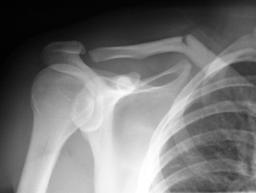

Clavicle Shaft Fractures

Imaging

• Radiographs

• views

• sitting/standing upright, standard AP view of bilateral shoulders

• additional views

• 15° cephalic tilt (ZANCA view) determine superior/inferior displacement

• may consider having the patient hold 5 to 10 lbs weight in affected hand